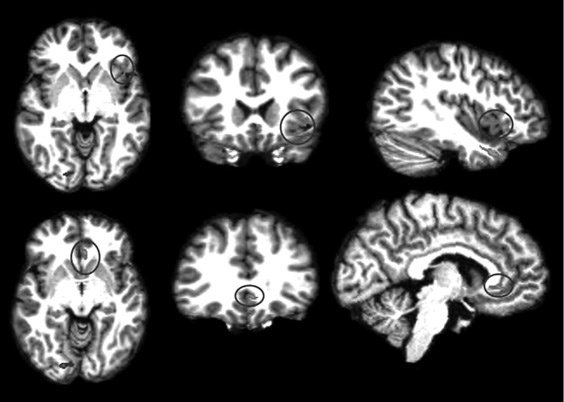

Анализируя далее научную литературу, мы пришли к выводу, что процесс поведенческого подражания с участием верхних отделов височной коры и эмоциональный (физиологический) резонанс, требующий участия островка, тоже имеют отношение к системе зеркальных нейронов. При подражании верхние отделы височной коры кодируют сложные процессы сенсорных следствий двигательных актов; при эмоциональном резонансе островок осуществляет физиологический и аффективный сдвиг, имитирующий его у другого человека. Исходя из параллелизма этих функций реципрокного действия (имитационной, физиологической и аффективной), мы можем использовать термин «резонансный контур», подразумевая, что в нем могут участвовать зеркальные нейроны, но не все компоненты этого контура двигательные, поэтому формально мы не можем назвать такой контур зеркальным. В нашем обсуждении мы примем во внимание это отличие и будем называть резонансный контур именно так, или будем прибегать к выражению «области, связанные с системой зеркальных нейронов» (рис. П.1 и П.2).

П.1

Иллюстрация к книге — Внимательный мозг. Научный взгляд на медитацию [i_014.jpg]

Рис. П.1, П.2. Функциональная МРТ, выполненная во время выполнения медитации осознавания дыхания. На снимках видна активация верхней височной извилины (рис. П.1) и активация островка и вентрального отдела передней поясной извилины (рис. П.2). Верхняя височная кора, островок и области срединной префронтальной коры (показанные здесь) вместе с системой зеркальных нейронов, как предполагается в тексте, содержат элементы «резонансного контура», которые активируются в ходе внимательного осознавания (снимки напечатаны с разрешения Сары Лазар © 2005)